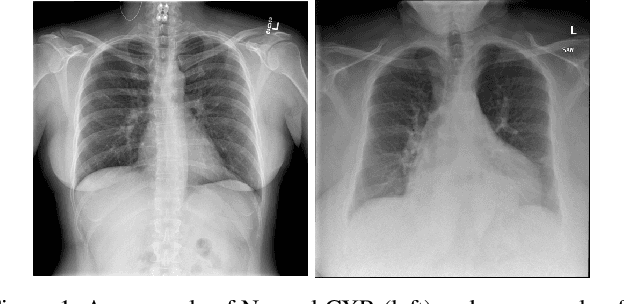

Abstract:Chest X-Rays (CXRs) are widely used for diagnosing abnormalities in the heart and lung area. Automatically detecting these abnormalities with high accuracy could greatly enhance real world diagnosis processes. Lack of standard publicly available dataset and benchmark studies, however, makes it difficult to compare various detection methods. In order to overcome these difficulties, we have used a publicly available Indiana CXR, JSRT and Shenzhen dataset and studied the performance of known deep convolutional network (DCN) architectures on different abnormalities. We find that the same DCN architecture doesn't perform well across all abnormalities. Shallow features or earlier layers consistently provide higher detection accuracy compared to deep features. We have also found ensemble models to improve classification significantly compared to single model. Combining these insight, we report the highest accuracy on chest X-Ray abnormality detection on these datasets. We find that for cardiomegaly detection, the deep learning method improves the accuracy by a staggering 17 percentage point compared to rule based methods. We applied the techniques to the problem of tuberculosis detection on a different dataset and achieved the highest accuracy. Our localization experiments using these trained classifiers show that for spatially spread out abnormalities like cardiomegaly and pulmonary edema, the network can localize the abnormalities successfully most of the time. One remarkable result of the cardiomegaly localization is that the heart and its surrounding region is most responsible for cardiomegaly detection, in contrast to the rule based models where the ratio of heart and lung area is used as the measure. We believe that through deep learning based classification and localization, we will discover many more interesting features in medical image diagnosis that are not considered traditionally.